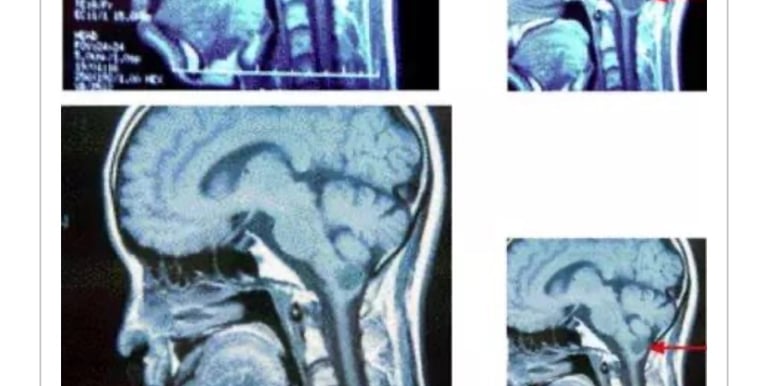

上咽喉癌/颅内转移(2002.3⇒2010.11)

A・M(1953年生、男性)2002年3月22日,因上咽喉癌出现颈部淋巴转移,同组织摘除后实施放疗化疗。此时的存活率仅有30%以下。

1个月后的4月22日来我院就诊。胸部以上部位癌症活性反应明显。

左侧颈部凹陷,由于放疗副作用患者唾液分泌困难。MW微波治疗从2002年5月13日开始连续治疗4天。

之患者情况稳定。

05年1月19日在脑外科被确诊左颞叶、顶叶、侧头均有转移(照片1)医生建议手术。

患者:「再也不想手术了。不管能治到什么程度都可以,能否用MW微波疗法继续治疗?」。

对此我对患者说「我不是脑外科专家,如果治疗效果不理想必须要手术时你能同意吗?」。

征得患者同意后。即于2005年1月20日开始,1天2次连续3天实施MW微波照射。之后11月、12月合计14次照射后,患者的癌症活性反应消失。

2006年1月27日的脑MRI显示肿瘤消除(照片2)。

患者A・M先生,住在北海道无法频繁来我院治疗,患者于2010年11月1日上咽喉癌复发死亡。患者从发病到死亡经过了8年,其中脑内转移消失保持接近5年。